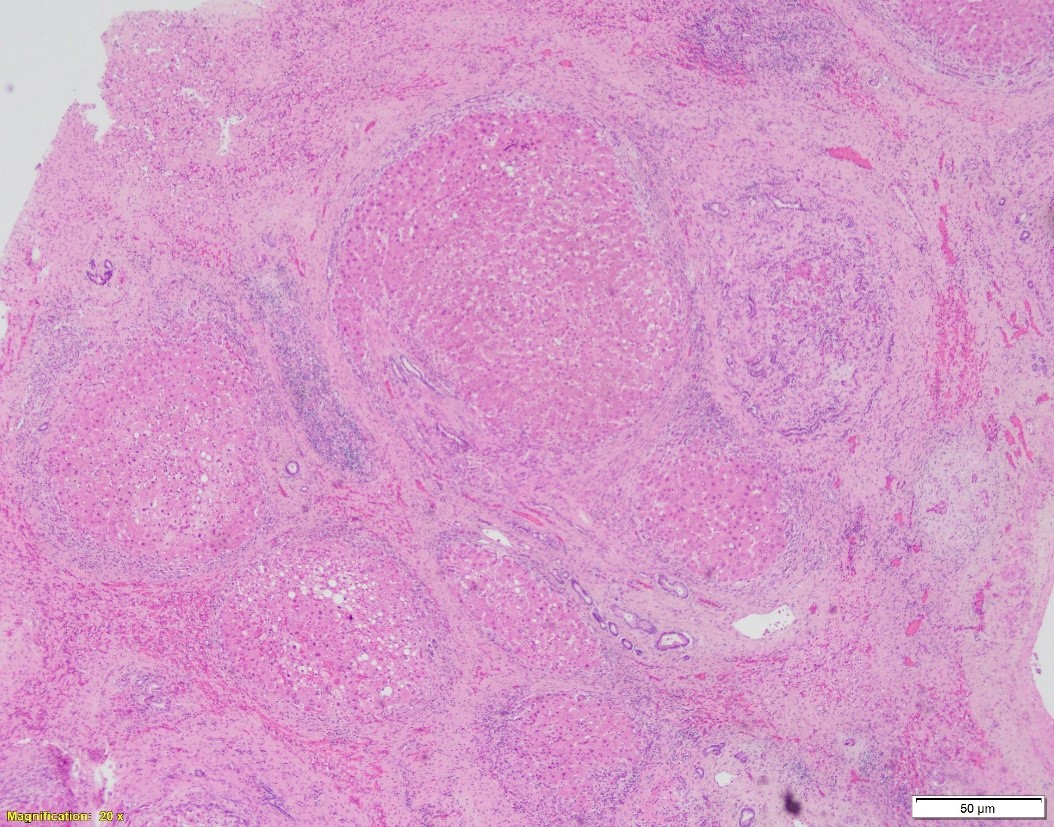

Patient is a 66-year-old female with NASH cirrhosis s/p OLT. Specimen: native liver explant. Pictures:

A. Hematoxylin and eosin, 20x. B. Hematoxylin and eosin, 100x. C. PAS w/diastase, 40x

In cirrhotic liver removed for transplantation, A1-antitrypsin deficiency grossly presents as micronodular or mixed micro- and macronodular pattern of cirrhosis. Microscopic findings include intracytoplasmic eosinophilic globules in periportal hepatocytes, which does not always correlate with the clinical liver disease. PAS w/diastase is helpful to distinguish A1-antitrypsin globules from glycogen. In infants, the globules may be absent or hard to detect; in these children, however, the disease may present as liver injury in form of neonatal hepatitis, cholestatic hepatitis, or extrahepatic biliary atresia, with variable degrees of fibrosis. In adults, besides the presence of A1AT globules, the changes may include mild portal inflammation and bile ductular proliferation, mild steatosis, and variable fibrosis.